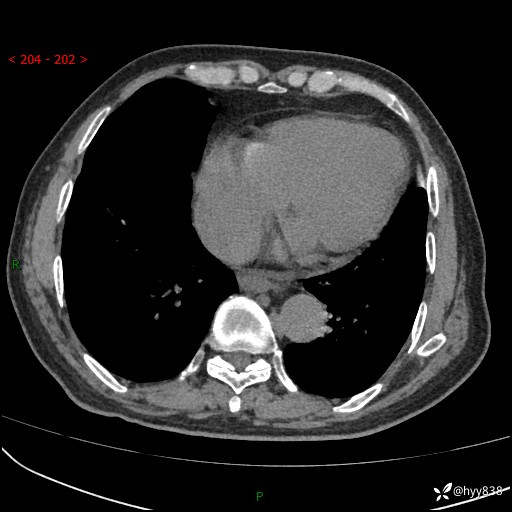

主诉:检查发现心脏肿物1周余。

现病史:患者一周余前因腹胀就诊我院消化科门诊,查心脏彩超提示右房内异常回声(粘液瘤?),无明显心慌、气喘、胸闷,无明显胸痛、咳嗽咳痰等不适,活动量增加后出现心慌、气喘不适。现为求进一步治疗,就诊我科,门诊遂以“心脏肿物”收入院。 自发病以来,精神睡眠一般,食欲尚可,大小便正常,体力下降,体重无明显变化。

胸部CT平扫+增强